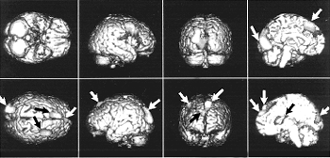

Член-корреспондент РАН С. В. Медведев Несмотря на все достижения современной науки, человеческий мозг остаётся самым загадочным объектом. С помощью сложнейшей тонкой аппаратуры учёные Института мозга человека Российской АН смогли „проникнуть“ в глубины мозга, не нарушая его работы, и выяснить, каким образом происходит запоминание информации, обработка речи, как формируются эмоции. Эти исследования помогают не только разобраться в том, как выполняет мозг свои важнейшие психические функции, но и разработать методы лечения тех людей, у которых они нарушены. Об этих и других работах Института мозга человека рассказывает его директор С.В. Медведев. Мозг против мозга — кто кого? Проблема исследования мозга человека, соотношения мозга и психики — одна из самых захватывающих задач, которые когда-либо возникали в науке. Впервые поставлена цель познать нечто, равное по сложности самому инструменту познания. Ведь всё, что до сих пор исследовалось — и атом, и галактика, и мозг животного — было проще, чем мозг человека. С философской точки зрения неизвестно, возможно ли в принципе решение этой задачи. Ведь, кроме приборов и методов, главным средством познания мозга остаётся опять-таки наш человеческий мозг. Обычно прибор, который изучает какое-то явление или объект, сложнее этого объекта, в этом же случае мы пытаемся действовать на равных — мозг против мозга. Грандиозность задачи привлекала многие великие умы: о принципах работы мозга высказывались и Гиппократ, и Аристотель, и Декарт и многие другие. В прошлом веке были обнаружены зоны мозга, отвечающие за речь, — по имени открывателей их называют области Брока и Вернике. Однако настоящее научное исследование мозга началось с работ нашего гениального соотечественника И.М. Сеченова. Далее — В.М. Бехтерев, И.П. Павлов… Здесь я остановлюсь в перечислении имён, так как выдающихся исследователей мозга в двадцатом веке много, и слишком велика опасность кого-нибудь пропустить (особенно из ныне здравствующих, не дай Бог). Были сделаны великие открытия, но возможности методик того времени для изучения человеческих функций весьма ограничены: психологические тесты, клинические наблюдения и начиная с тридцатых годов электроэнцефалограмма. Это всё равно, что пытаться узнать, как работает телевизор, по гудению ламп и трансформаторов или по температуре футляра, либо попробовать понять роль составляющих его блоков, исходя из того, что произойдёт с телевизором, если этот блок разбить. Однако устройство мозга, его морфологию изучили уже довольно хорошо. А вот представления о функционировании отдельных нервных клеток были очень отрывочными. Таким образом, не хватало полноты знаний о кирпичиках, составляющих мозг, и необходимых инструментов для их исследования. Два прорыва в исследованиях мозга человека Реально первый прорыв в познании мозга человека был связан с применением метода долгосрочных и краткосрочных имплантированных электродов для диагностики и лечения больных. В то же время учёные начали понимать, как работает отдельный нейрон, как происходит передача информации от нейрона к нейрону и по нерву. В нашей стране первыми в условиях непосредственного контакта с мозгом человека стали работать академик Н.П. Бехтерева и её сотрудники. Так были получены данные о жизни отдельных зон мозга, о соотношении его важнейших разделов — коры и подкорки и многие другие. Однако мозг состоит из десятков миллиардов нейронов, а с помощью электродов можно наблюдать лишь за десятками, да и то в поле зрения исследователей часто попадают не те клетки, которые нужны для исследования, а те, что оказались рядом с лечебным электродом. Тем временем в мире совершалась техническая революция. Новые вычислительные возможности позволили вывести на новый уровень исследование высших функций мозга с помощью электроэнцефалографии и вызванных потенциалов. Возникли и новые методы, позволяющие „заглянуть внутрь“ мозга: магнитоэнцефалография, функциональная магниторезонансная томография и позитронно-эмиссионная томография. Всё это создало фундамент для нового прорыва. Он действительно произошёл в середине восьмидесятых годов. В это время научный интерес и возможность его удовлетворения совпали. Видимо, поэтому Конгресс США объявил девяностые годы десятилетием изучения человеческого мозга. Эта инициатива быстро стала международной. Сейчас во всём мире над исследованием человеческого мозга трудятся сотни лучших лабораторий. Надо сказать, что у нас в то время в верхних эшелонах власти было много умных и болеющих за державу людей. Поэтому и в нашей стране поняли необходимость исследования мозга человека и предложили мне на базе коллектива, созданного и руководимого академиком Бехтеревой, организовать научный центр по исследованию мозга — Институт мозга человека РАН. Главное направление деятельности института: фундаментальные исследования организации мозга человека и его сложных психических функций — речи, эмоций, внимания, памяти. Но не только. Одновременно учёные должны вести поиск методов лечения тех больных, у которых эти важные функции нарушены. Соединение фундаментальных исследований и практической работы с больными было одним из основных принципов деятельности института, разработанных его научным руководителем Натальей Петровной Бехтеревой. Недопустимо ставить эксперименты на человеке. Поэтому большая часть исследований мозга проводится на животных. Однако есть явления, которые могут быть изучены только на человеке. Например, сейчас молодой сотрудник моей лаборатории защищает диссертацию об обработке речи, её орфографии и синтаксиса в различных структурах мозга. Согласитесь, что это трудно исследовать на крысе. Институт специально ориентирован на исследование того, что нельзя изучать на животных. Мы проводим психофизиологические исследования на добровольцах с применением так называемой неинвазивной техники, не „залезая“ внутрь мозга и не причиняя человеку особенных неудобств. Так осуществляются, например, томографические обследования или картирование мозга с помощью электроэнцефалографии. Но бывает, что болезнь или несчастный случай „ставят эксперимент“ на человеческом мозге — например, у больного нарушается речь или память. В этой ситуации можно и нужно исследовать те области мозга, работа которых нарушена. Или, наоборот, у пациента утерян или повреждён кусочек мозга, и учёным предоставляется возможность изучить, какие свои „обязанности“ мозг не может выполнять с таким нарушением. Но просто наблюдать за такими пациентами , мягко говоря, неэтично, и в нашем институте не только исследуют больных с различными повреждениями мозга, но и помогают им, в том числе и с помощью новейших, разработанных нашими сотрудниками методов лечения. Для этой цели при институте существует клиника на 160 коек. Две задачи — исследование и лечение — неразрывно связаны в работе наших сотрудников. У нас прекрасные высококвалифицированниые доктора и медсёстры. Без этого нельзя — ведь мы на переднем крае науки, и нужна высочайшая квалификация, чтобы реализовать новые методики. Практически каждая лаборатория института замкнута на отделения клиники, и это залог непрерывного появления новых подходов. Кроме стандартных методов лечения у нас проводят хирургическое лечение эпилепсии и паркинсонизма, психохирургические операции, лечение мозговой ткани магнитостимуляцией, лечение афазии с помощью электростимуляции, а также многое другое. В клинике лежат тяжёлые больные, и бывает удаётся помочь им в случаях, считавшихся безнадёжными. Конечно, это возможно не всегда. Вообще, когда слышишь какие-либо безграничные гарантии в лечении людей, это вызывает очень серьёзные сомнения. Будни и звёздные часы лабораторий В каждой лаборатории есть свои достижения. Например, лаборатория, которой руководит профессор В.А. Илюхина, ведёт разработки в области нейрофизиологии функциональных состояний головного мозга. Что это такое? Попробую объяснить на простом примере. Каждый знает, что одна и та же фраза иногда воспринимается человеком диаметрально противоположно в зависимости от того, в каком состоянии он находится: болен или здоров, возбуждён или спокоен. Это похоже на то, как одна и та же нота, извлекаемая, например, из органа, имеет разный тембр в зависимости от регистра. Наш мозг и организм — сложнейшая многорегистровая система, где роль регистра играет состояние человека. Можно сказать, что весь спектр взаимоотношений человека с окружающей средой определяется его функциональным состоянием. Оно определяет и возможность „срыва“ оператора за пультом управления сложнейшей машиной, и реакцию больного на принимаемое лекарство. В лаборатории профессора Илюхиной исследуют функциональные состояния, а также то, какими параметрами они определяются, как эти параметры и сами состояния зависят от регуляторных систем организма, как внешние и внутренние воздействия изменяют состояния, иногда вызывая болезнь, и как в свою очередь состояния мозга и организма влияют на течение заболевания и действие лекарственных средств. С помощью полученных результатов можно сделать правильный выбор между альтернативными путями лечения. Проводится и определение приспособительных возможностей человека: насколько он будет устойчив при каком-либо лечебном воздействии, стрессе. Очень важной задачей занимается лаборатория нейроиммунологии. Нарушения иммунорегуляции часто приводят к возникновению тяжёлых заболеваний головного мозга. Это состояние надо диагностировать и подобрать лечение — иммунокоррекцию. Типичный пример нейроиммунного заболевания — рассеянный склероз, изучением которого в институте занимается лаборатория под руководством профессора И.Д. Столярова. Не так давно он вошёл в совет Европейского комитета, занимающегося исследованием и лечением рассеянного склероза. В двадцатом веке человек начал активно изменять окружающий его мир, празднуя победу над природой, но оказалось, что праздновать рано: при этом обостряются проблемы, созданные самим человеком, так называемые техногенные. Мы живём под воздействием магнитных полей, при свете мигающих газосветных ламп, часами смотрим на дисплей компьютера, говорим по мобильному телефону… Всё это далеко не безразлично для организма человека: например, хорошо известно, что мигающий свет способен вызвать эпилептический припадок. Можно устранить вред, наносимый при этом мозгу, очень простыми мерами — закрыть один глаз. Чтобы резко снизить „поражающее действие“ радиотелефона (кстати, оно ещё точно не доказано), можно просто изменить его конструкцию так, чтобы антенна была направлена вниз и мозг не облучался. Этими исследованиями занимается лаборатория под руководством доктора медицинских наук Е.Б. Лыскова. Например, он и его сотрудники показали, что воздействие переменного магнитного поля отрицательно сказывается на процессе обучения. На уровне клеток работа мозга связана с химическими превращениями различных веществ, поэтому для нас важны результаты, полученные в лаборатории молекулярной нейробиологии, руководимой профессором С.А. Дамбиновой. Сотрудники этой лаборатории разрабатывают новые методы диагностики заболеваний мозга, проводят поиск химических веществ белковой природы, которые способны нормализовать нарушения в ткани мозга при паркинсонизме, эпилепсии, наркотической и алкогольной зависимости. Оказалось, что употребление наркотиков и алкоголя приводит к разрушению нервных клеток. Их фрагменты, попадая в кровь, побуждают иммунную систему вырабатывать так называемые „аутоантитела“. „Аутоантитела“ остаются в крови ещё долгое время, даже у людей, переставших употреблять наркотики. Это своеобразная память организма, хранящая информацию об употреблении наркотиков. Если измерить в крови человека количество аутоантител к специфическим фрагментам нервных клеток, можно поставить диагноз „наркомания“ даже через несколько лет после того, как человек перестал употреблять наркотики. Можно ли «перевоспитать» нервные клетки? Одно из самых современных направлений в работе института — стереотаксис. Это медицинская технология, обеспечивающая возможность малотравматичного, щадящего, прицельного доступа к глубоким структурам головного мозга и дозированное воздействие на них. Это нейрохирургия будущего. Вместо „открытых“ нейрохирургических вмешательств, когда, чтобы достичь мозга, делают большую трепанацию, предлагаются малотравматичные, щадящие воздействия на головной мозг. В развитых странах, прежде всего в США, клинический стереотаксис занял достойное место в нейрохирургии. В США в этой сфере сегодня работают около 300 нейрохирургов — членов Американского стереотаксического общества. Основа стереотаксиса — математика и точные приборы, обеспечивающие прицельное погружение в мозг тонких инструментов. Они позволяют „заглянуть“ в мозг живого человека. При этом используется позитронно-эмиссионная томография, магниторезонансная томография, компьютерная рентгеновская томография. „Стереотаксис — мерило методической зрелости нейрохирургии“ — мнение ныне покойного нейрохирурга Л.В. Абракова. Для стереотаксического метода лечения очень важно знание роли отдельных „точек“ в мозге человека, понимание их взаимодействия, знание того, где и что именно нужно изменить в мозге для лечения той или иной болезни. В институте существует лаборатория стереотаксических методов, которой руководит доктор медицинских наук, лауреат Государственной премии СССР А.Д. Аничков. По существу, это ведущий стереотаксический центр России. Здесь родилось самое современное направление — компьютерный стереотакcис с программно-математическим обеспечением, которое осуществляется на электронной вычислительной машине. До наших разработок стереотаксические расчёты проводились нейрохирургами вручную во время операции, сейчас же у нас разработаны десятки стереотаксических приборов; некоторые прошли клиническую апробацию и способны решать самые сложные задачи. Совместно с коллегами из ЦНИИ „Электроприбор“ создана и впервые в России серийно выпускается компьютеризированная стереотаксическая система, которая по ряду основных показателей превосходит аналогичные зарубежные образцы. Как выразился неизвестный автор, „наконец, робкие лучи цивилизации осветили наши тёмные пещеры“. В нашем институте стереотаксис применяется при лечении больных, страдающих двигательными нарушениями (паркинсонизмом, болезнью Паркинсона, хореей Гентингтона и другими), эпилепсией, неукротимыми болями (в частности, фантомно-болевым синдромом), некоторыми психическими нарушениями. Кроме того, стереотаксис используется для уточнения диагноза и лечения некоторых опухолей головного мозга, для лечения гематом, абсцессов, кист мозга. Стереотаксические вмешательства (как и все остальные нейрохирургические вмешательства) предлагаются больному только в том случае, если исчерпаны все возможности медикаментозного лечения и само заболевание угрожает здоровью пациента или лишает его трудоспособности, делает асоциальным. Все операции производятся только при согласии больного и его родственников, после консилиума специалистов разного профиля. Существуют два вида стереотаксиса. Первый, нефункциональный, применяется тогда, когда в глубине мозга имеется какое-то органическое поражение, например опухоль. Если её удалять с помощью обычной техники, придётся затронуть здоровые, выполняющие важные функции структуры мозга и больному случайно может быть нанесён вред, иногда даже несовместимый с жизнью. Предположим, что опухоль хорошо видна с помощью магниторезонансного и позитронно-эмиссионного томографов. Тогда можно рассчитать её координаты и ввести с помощью малотравматичного тонкого щупа радиоактивные вещества, которые выжгут опухоль и за короткое время распадутся. Повреждения при проходе сквозь мозговую ткань минимальны, а опухоль будет уничтожена. Мы провели уже несколько таких операций, бывшие пациенты живут до сих пор, хотя при традиционных методах лечения у них не было никакой надежды. Суть этого метода в том, что мы устраняем „дефект“, который чётко видим. Главная задача — решить, как до него добраться, какой путь выбрать, чтобы не задеть важные зоны, какой метод устранения „дефекта“ выбрать. Принципиально другая ситуация при „функциональном“ стереотаксисе, который тоже применяется при лечении психических заболеваний. Причина болезни часто заключается в том, что одна маленькая группа нервных клеток или несколько таких групп работают неправильно. Они либо не выделяют необходимые вещества, либо выделяют их слишком много. Клетки могут быть патологически возбуждены, и тогда стимулируют „нехорошую“ активность других, здоровых клеток. Эти „сбившиеся с пути“ клетки надо найти и либо уничтожить, либо изолировать, либо „перевоспитать“ с помощью электростимуляции. В такой ситуации нельзя „увидеть“ поражённый участок. Мы должны его вычислить чисто теоретически, как астрономы вычислили орбиту Нептуна. Именно здесь для нас особенно важны фундаментальные знания о принципах работы мозга, о взаимодействии его участков, о функциональной роли каждого участка мозга. Мы используем результаты стереотаксической неврологии — нового направления, разработанного в институте покойным профессором В.М. Смирновым. Стереотаксическая неврология — это „высший пилотаж“, однако именно на этом пути нужно искать возможность лечения многих тяжёлых заболеваний, в том числе и психических. Результаты наших исследований и данные других лабораторий указывают на то, что практически любая, даже очень сложная психическая деятельность мозга обеспечивается распределённой в пространстве и изменчивой во времени системой, состоящей из звеньев различной степени жёсткости. Понятно, что вмешиваться в работу такой системы очень трудно. Тем не менее сейчас мы это умеем: например, можем создать новый центр речи взамен разрушенного при травме. При этом происходит своеобразное „перевоспитание“ нервных клеток. Дело в том, что существуют нервные клетки, которые от рождения готовы к своей работе, но есть и другие, которые „воспитываются“ в процессе развития человека. Научаясь выполнять одни задачи, они забывают другие, но не навсегда. Даже пройдя „специализацию“, они в принципе способны взять на себя выполнение каких-то других задач, могут работать и по-другому. Поэтому можно попытаться заставить их взять на себя работу утраченных нервных клеток, заменить их. Нейроны мозга работают как команда корабля: один хорошо умеет вести судно по курсу, другой — стрелять, третий — готовить пищу. Но ведь и стрелка можно научить готовить борщ, а кока — наводить орудие. Нужно только объяснить им, как это делается. В принципе это естественный механизм: если травма мозга произошла у ребёнка, у него нервные клетки самопроизвольно „переучиваются“. У взрослых же для „переучивания“ клеток нужно применять специальные методы. Этим и занимаются исследователи — пытаются стимулировать одни нервные клетки выполнять работу других, которые уже нельзя восстановить. В этом направлении уже получены хорошие результаты: например, некоторых пациентов с нарушением области Брока, отвечающей за формирование речи, удалось обучить говорить заново. Другой пример — лечебное воздействие психохирургических операций, направленных на „выключение“ структур области мозга, называемой лимбической системой. При разных болезнях в разных зонах мозга возникает поток патологических импульсов, которые циркулируют по нервным путям. Эти импульсы появляются в результате повышенной активности зон мозга, и такой механизм приводит к целому ряду хронических заболеваний нервной системы, таких, как паркинсонизм, эпилепсия, навязчивые состояния. Пути, по которым проходит циркуляция патологических импульсов, надо найти и максимально щадяще „выключить“. В последние годы проведены многие сотни (особенно в США) стереотаксических психохирургических вмешательств для лечения больных, страдающих некоторыми психическими нарушениями (прежде всего, навязчивыми состояниями), у которых оказались неэффективными нехирургические методы лечения. По мнению некоторых наркологов, наркоманию тоже можно рассматривать как разновидность такого рода расстройства, поэтому в случае неэффективности медикаментозного лечения может быть рекомендовано стереотаксическое вмешательство. Детектор ошибок Очень важное направление работы института — исследование высших функций мозга: внимания, памяти, мышления, речи, эмоций. Этими проблемами занимаются несколько лабораторий, в том числе та, которой руковожу я, лаборатория академика Н.П. Бехтеревой, лаборатория доктора биологических наук Ю.Д. Кропотова. Присущие только человеку функции мозга исследуются с помощью различных подходов: используется „обычная“ электроэнцефалограмма, но на новом уровне картирования мозга, изучение вызванных потенциалов, регистрация этих процессов совместно с импульсной активностью нейронов при непосредственном контакте с мозговой тканью — для этого применяются имплантированные электроды и техника позитронно-эмиссионной томографии. Работы академика Н.П. Бехтеревой в этой области достаточно широко освещались в научной и научно-популярной печати. Она начала планомерное исследование психических процессов в мозге ещё тогда, когда большинство учёных считали это практически непознаваемым, делом далёкого будущего. Как хорошо, что хотя бы в науке истина не зависит от позиции большинства. Многие из тех, кто отрицал возможность таких исследований, теперь считают их приоритетными. В рамках этой статьи можно упомянуть только о самых интересных результатах, например о детекторе ошибок. Каждый из нас сталкивался с его работой. Представьте, что вы вышли из дому и уже на улице вас начинает терзать странное чувство — что-то не так. Вы возвращаетесь — так и есть, забыли выключить свет в ванной. То есть, вы забыли выполнить обычное, стереотипное действие — щёлкнуть выключателем, и этот пропуск автоматически включил контрольный механизм в мозге. Этот механизм в середине шестидесятых был открыт Н.П. Бехтеревой и её сотрудниками. Несмотря на то, что результаты были опубликованы в научных журналах, в том числе и зарубежных, сейчас они „переоткрыты“ на Западе людьми, знающими работы наших учёных, но не гнушающимися прямым заимствованием у них. Исчезновение великой державы привело и к тому, что в науке стало больше случаев прямого плагиата. Детекция ошибок может стать и болезнью, когда этот механизм работает больше, чем нужно, и человеку всё время кажется, что он что-то забыл. В общих чертах нам сегодня ясен и процесс запуска эмоций на уровне мозга. Почему один человек с ними справляется, а другой — „западает“, не может вырваться из замкнутого круга однотипных переживаний? Оказалось, что у „стабильного“ человека изменения обмена веществ в мозге, связанные, например, с горем, обязательно компенсируются направленными в другую сторону изменениями обмена веществ в других структурах. У „нестабильного“ же человека эта компенсация нарушена. Кто отвечает за грамматику? Очень важное направление работы — так называемое микрокартирование мозга. В наших совместных исследованиях обнаружены даже такие механизмы, как детектор грамматической правильности осмысленной фразы. Например, „голубая лента“ и „голубой лента“. Смысл понятен в обоих случаях. Но есть одна „маленькая, но гордая“ группа нейронов, которая „взвивается“, когда грамматика нарушена, и сигнализирует об этом мозгу. Зачем это нужно? Вероятно, затем, что понимание речи часто идёт в первую очередь за счёт анализа грамматики (вспомним „глокую куздру“ академика Щербы). Если с грамматикой что-то не так, поступает сигнал — надо проводить добавочный анализ.

Найдены микроучастки мозга, которые отвечают за счёт, за различение конкретных и абстрактных слов. Показаны различия в работе нейронов при восприятии слова родного языка (чашка), квазислова родного языка (чохна) и слова иностранного (вахт — время по-азербайджански). В этой деятельности по-разному участвуют нейроны коры и глубоких структур мозга. В глубоких структурах в основном наблюдается увеличение частоты электрических разрядов, не очень „привязанное“ к какой-то определённой зоне. Эти нейроны как бы любую задачу решают всем миром. Совершенно другая картина в коре головного мозга. Один нейрон словно говорит: „А ну-ка, ребята, помолчите, это моё дело, и я буду выполнять его сам“. И действительно, у всех нейронов, кроме некоторых, понижается частота импульсации, а у „избранников“ повышается. Благодаря технике позитронно-эмиссионной томографии (или сокращённо ПЭТ) стало возможно детальное изучение одновременно всех областей мозга, отвечающих за сложные „человеческие“ функции. Суть метода состоит в том, что малое количество изотопа вводят в вещество, участвующее в химических превращениях внутри клеток мозга, а затем наблюдают, как меняется распределение этого вещества в интересующей нас области мозга. Если к этой области усиливается приток глюкозы с радиоактивной меткой — значит, увеличился обмен веществ, что говорит об усиленной работе нервных клеток на этом участке мозга. А теперь представьте, что человек выполняет какое-то сложное задание, требующее от него знания правил орфографии или логического мышления. При этом у него наиболее активно работают нервные клетки в области мозга, „ответственной“ именно за эти навыки. Усиление работы нервных клеток можно зарегистрировать с помощью ПЭТ по увеличению кровотока в активизированной зоне. Таким образом удалось определить, какие области мозга „отвечают“ за синтаксис, орфографию, смысл речи и за решение других задач. Например, известны зоны, которые активизируются при предъявлении слов, неважно, надо их читать или нет. Есть и зоны, которые активизируются, чтобы „ничего не делать“, когда, например, человек слушает рассказ, но не слышит его, следя за чем-то другим. Что такое внимание? Не менее важно понять, как „работает“ внимание у человека. Этой проблемой в нашем институте занимается и моя лаборатория, и лаборатория Ю.Д. Кропотова. Исследования ведутся совместно с коллективом учёных под руководством финского профессора Р. Наатанена, который открыл так называемый механизм непроизвольного внимания. Чтобы понять, о чём идёт речь, представьте ситуацию: охотник крадётся по лесу, выслеживая добычу. Но он и сам является добычей для хищного зверя, которого не замечает, потому что настроен только на поиск оленя или зайца. И вдруг случайный треск в кустах, может быть, и не очень заметный на фоне птичьего щебета и шума ручья, мгновенно переключает его внимание, подаёт сигнал: „Рядом опасность“. Механизм непроизвольного внимания сформировался у человека в глубокой древности, как охранный механизм, но работает и сейчас: например, водитель ведёт машину, слушает радио, слышит крики детей, играющих на улице, воспринимает все звуки окружающего мира, внимание его рассеянно, и вдруг тихий стук мотора мгновенно переключает его внимание на машину — он осознаёт, что с двигателем что-то не в порядке (кстати, это явление похоже на детектор ошибок). Такой переключатель внимания работает у каждого человека. Мы обнаружили зоны, которые активизируются на ПЭТ при работе этого механизма, а Ю.Д. Кропотов исследовал его с помощью метода имплантированных электродов. Иногда в самой сложной научной работе бывают смешные эпизоды. Так было, когда мы в спешке закончили эту работу перед очень важным и престижным симпозиумом. Ю.Д. Кропотов и я поехали на симпозиум делать доклады, и только там с удивлением и „чувством глубокого удовлетворения“ неожиданно выяснили, что активизация нейронов происходит в одних и тех же зонах. Да, иногда двоим сидящим рядом надо поехать в другую страну, чтобы поговорить.